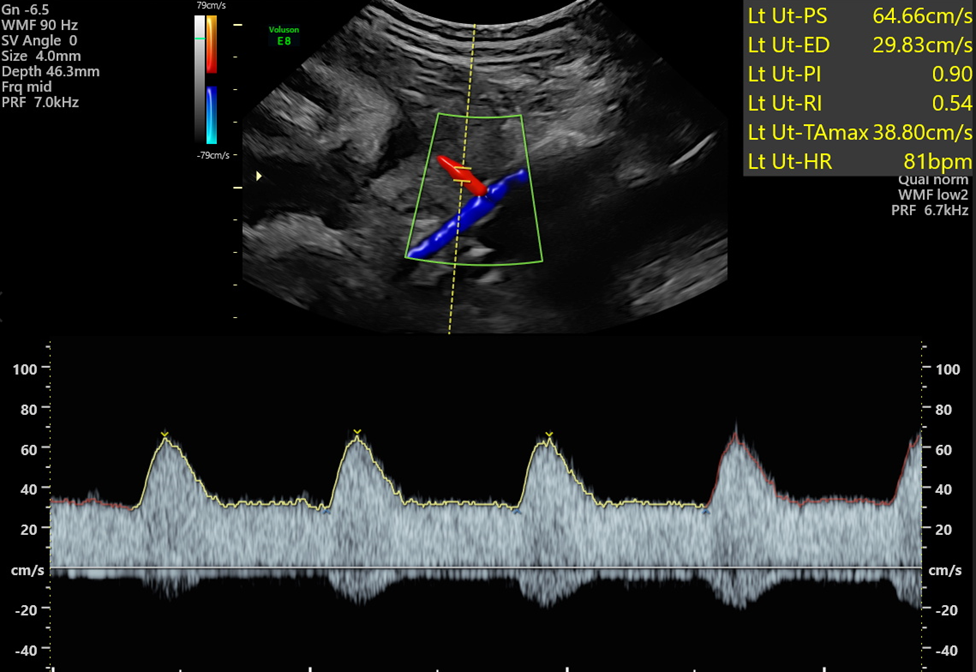

- Optimise your spectral trace by adjusting the sweep speed and baseline to ensure you can trace at least 3 complete waveforms. Auto-trace can then be applied, and Doppler sensitivity altered to ensure the peaks and troughs of the waveforms are correctly identified.

- Each uterine artery should be sampled at least 3 times, 1.5cm downstream (anterior to the external iliac vessels). The lowest PI should be reported if all the traces are of equal quality.